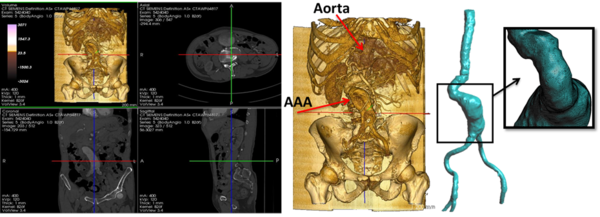

1.4.1.1 4D flow cardiovascular magnetic resonance imaging

At present, 4D flow cardiovascular magnetic resonance imaging (4D CMRI) sequences are being a promising tool to visualize and quantify 4D (3D+t) blood flow. From these sequences the raw data can be obtained and conveniently processed, allowing visualization of the blood flow patterns in any segment of the cardiovascular tree[71][72][73]. Nevertheless, the visualization of these images entails an important manual work, becoming a very time-dependent task and then turning out to be not useful in the current clinical practice. Therefore, it is important to improve the technology and the methods of automatic representation of the 4D blood flows, in particular for the WSS analysis. In chapter 5, it is demonstrated that 4D flow CMRI technique is a reliable tool to provide the boundary conditions for the Computational Fluid Dynamics(CFD) in order to estimate the WSS within the entire thoracic aorta in a short computation time. Our image-based CFD methodology exploits the morphological MRI for geometry modelling and 4D flow CMRI for setting the boundary conditions for the fluid dynamics modelling. The aim is to evaluate visualization of well-defined aortic blood flow features and the associated wall shear stress by the combination of both techniques. In that sense, CIMNE has developed a home-made ad-hoc software (Aorta4D) oriented to make progress in this field of work [72][74][73]. Aorta4D will afford analysis and spatially visualization of the registered 3-directional blood flow velocities, and perform a 3D semi-automatic segmentation based on the 4D flow CMRI data.

6.1 Qualitative evaluation of flow patterns in the Ascending aorta with 4D phase contrast sequences

4D Phase Contrast Cardiac Magnetic Resonance(4D-PC-CMR) sequences allow to obtain three-dimensional flow images (see section 1.4.1.1) and to analyze of the patient-specific characteristics of intravascular flows under normal and pathological conditions. In clinical practice, these sequences allow to advance the understanding of the pathophysiology of vascular diseases through the interaction between flow and anatomy. Besides of this, it also help to understand the origin of diagnostic errors of 2D flow PC sequences. The aim of this study is to describe and characterize qualitatively different patterns of systolic flow in the Ascending Aorta(AoAsc) against to its aortic diameter with different degrees of root dilatation and against the different aortic valve pathologies using 4D PC Cardio MR sequences.All the patients (31 patients) who participated in this trial were volunteered and provided written consent to be part of this study. This study was reviewed and approved by the Ethics Committee of the Hospital Sant Pau i Creu Blanca, Barcelona, Spain. The 31 patients have different aortic problems, 12 patients suffer cardiomyopathy, 6 patients have a dilated aorta, 4 patients have aortic valve disease, 1 patient has a mitral valve disease, 1 patient has an atrial fibrillation and another suffers syncope, as well as 5 were healthy volunteers. For each patient an anatomy/flow cross-sectional of AoAsc was done. The flow pattern studied was: (i) at the Valsalva sinus (SV), where the flow adopts a uniformity velocity with a peak in the middle of the aorta (see figure 11.A and 11.B) or an eccetric flow jet with a maximun speed located at the periphery (see figure 11.C and 11.D), and (ii) at the AoAsc level, where the flow keep constast along the systole phase (see figure 11.A and 11.B) or the Systolic Turbulent Flow (FTS) can be defined as vortices or circular paths in opposite direction to the normal aortic systolic flow (see figure 11.D and 11.E). The AoAsc diameter was measured to the level of the bifurcation of the pulmonary artery, and the elongation of the aorta was defined as the maximum distance from the front wall of the AoAsc to the rear wall of the descending aorta at the level also to the bifurcation of the pulmonary artery. Jet's direction is defined as maximum velocity in the streamline related to the perpendicular plane at the aortic root.

In 29 patients (93.5%) the left ventricular ejection fraction was normal. The aortic valve was bicuspid in 4 patients and 3 of them show a dilated AoAsc.The average diameter of the AoAsc was 16.804.41mm. The mean aortic elongation diameter was 5.150.99cm. From the 4D sequences, 15 patients have a central jet at the Valsalva sinus (48.4%) and 16 patients have an eccentric jet (51.6% 10 patients have laminar flow at the AoAsc level (32%), 13 patients show a vortex during the systolic phase(42%) and 8 patient during the protosystolic phase(26%) (see figure 11). Statistical correlation between FTS against the AoAsc diameter and elongation of the aorta was done 12. The analysis shows that the diameter of the AoAsc has a significant linear relationship with the flow pattern in aortic systolic, which indicates higher prevalence of turbulence flow (proto-systolic vs systolic) for a higher aortic diameter (figure 12). The flow characteristics in the AoAsc were analyzed by two independent clinicians getting a good concordance. The jet eccentricity in the SV indicates a trend (p = 0.06) for the FTS origin in AoAsc. The presence of a bicuspid valve is also associated with the formation of vortices (p = 0.047), although when it is adjusted by the AoAsc's diameter, statistical significance (P = 0.48) decreases.

The flow pattern during systolic phase in the ascending aorta changes progressively from laminar flow with directional jet in not-dilated aortas to turbulent flow with eccentricity jet in dilated aortas. Other factors, such as bicuspid aortic valve can increase the turbulence effect but there are not essential to provoke it. This study was done in collaboration with Dr.Francecs Carreras, Dr.Chi-Hion Pedro Li and Dr.Xavier Alomar from Hospital Sant Pau i Creu Blanca and Clinica Creu Blanca, Barcelona, Spain, respectively. The equipment used was a Magnetom Verio 3T Siemens, Erlangen, Germany.